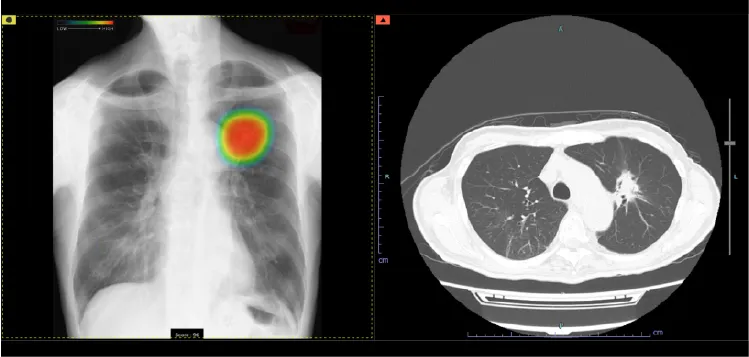

CT(コンピュータ断層装置)

CTは Computed Tomography(コンピュータ断層撮影) の略で、X線を使って体の断面を撮影する装置です。体の内部構造を詳しく画像化できるため、さまざまな病気の発見に役立ちます。近年の技術進歩により、0.5mm間隔で断層画像を撮影できるため、ごく小さな病変も見つけることが可能になりました。また、得られた断面画像を重ね合わせることで、立体的な3D画像を作成することもできます。さらに、必要に応じて 造影剤 を使用すると、腫瘍などの病変部位がより明瞭に写り、周囲の血管の走行や栄養血管の状態を詳しく把握することができます。ただし、造影剤には副作用の可能性があり、また腎機能が著しく低下している場合には使用できないことがあります。造影剤を使うかどうかは、検査内容に応じて医師が判断します。

GEヘルスケア・ジャパン株式会社 Revolution Maxima

当院ではGE社製の64列マルチスライスCTを導入しています。被ばく低減可能な逐次近似画像構成法ASiR-VソフトウェアやAI技術を駆使した次世代ワークフローを搭載した最新のCTで検査が行えます。